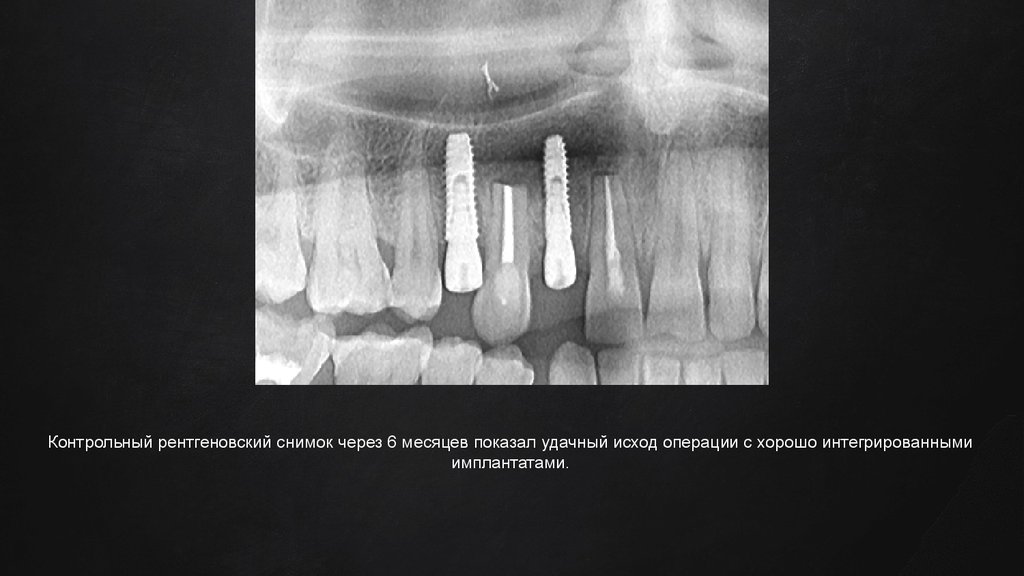

19.

Контрольный рентгеновский снимок через 6 месяцев показал удачный исход операции с хорошо интегрированными

имплантатами.